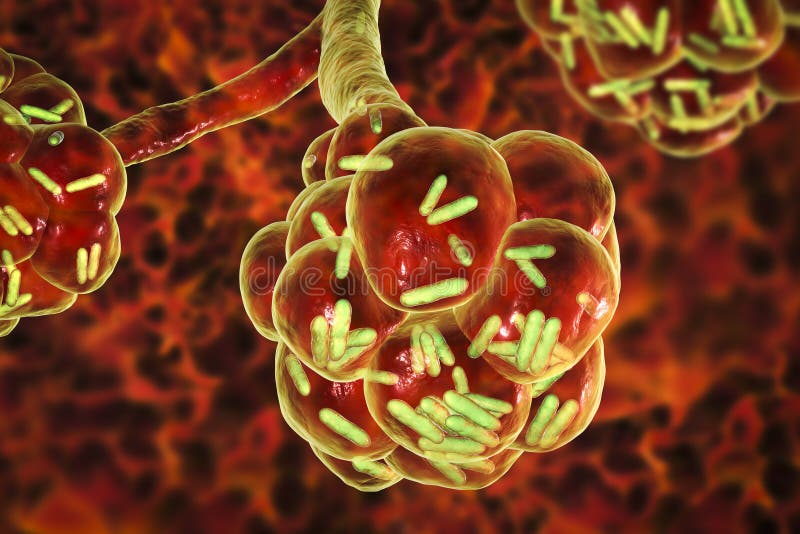

Фотографии бактерий, вызывающих бактериальные пневмонии у животных

Раздел: Другие животные